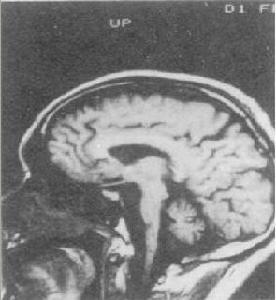

酒中毒性小腦變性酒中毒性小腦變性症是以運動失調為主要症狀病理學上是以小腦及其傳入、傳出途徑的變性為主體的疾病,臨床上是以肢體共濟失調和構音障礙為主要特徵。獲得型小腦變性後天的中毒性和代謝性原因引起的小腦變性和共濟失調。酒中毒性小腦變性是嗜酒者常見的小腦變性發病率約為Wernicke腦病的2倍臨床特點為步態不穩步距增寬。CT和MRI研究表明慢性酒中毒病人幾乎都有小腦萎縮小腦蚓部上端萎縮較重蚓部上端血流量減少和糖代謝率下降明顯。

診斷:根據慢性酒中毒的病史典型的小腦共濟失調的症狀體徵CT或MRI發現小腦蚓部上端萎縮排除其他原因的小腦萎縮和小腦變性家族史,診斷即可成立。